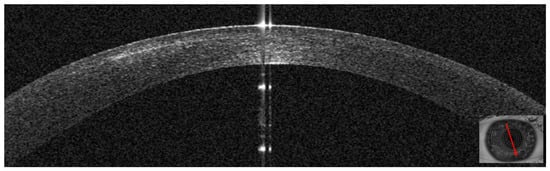

3.1. Patient #1